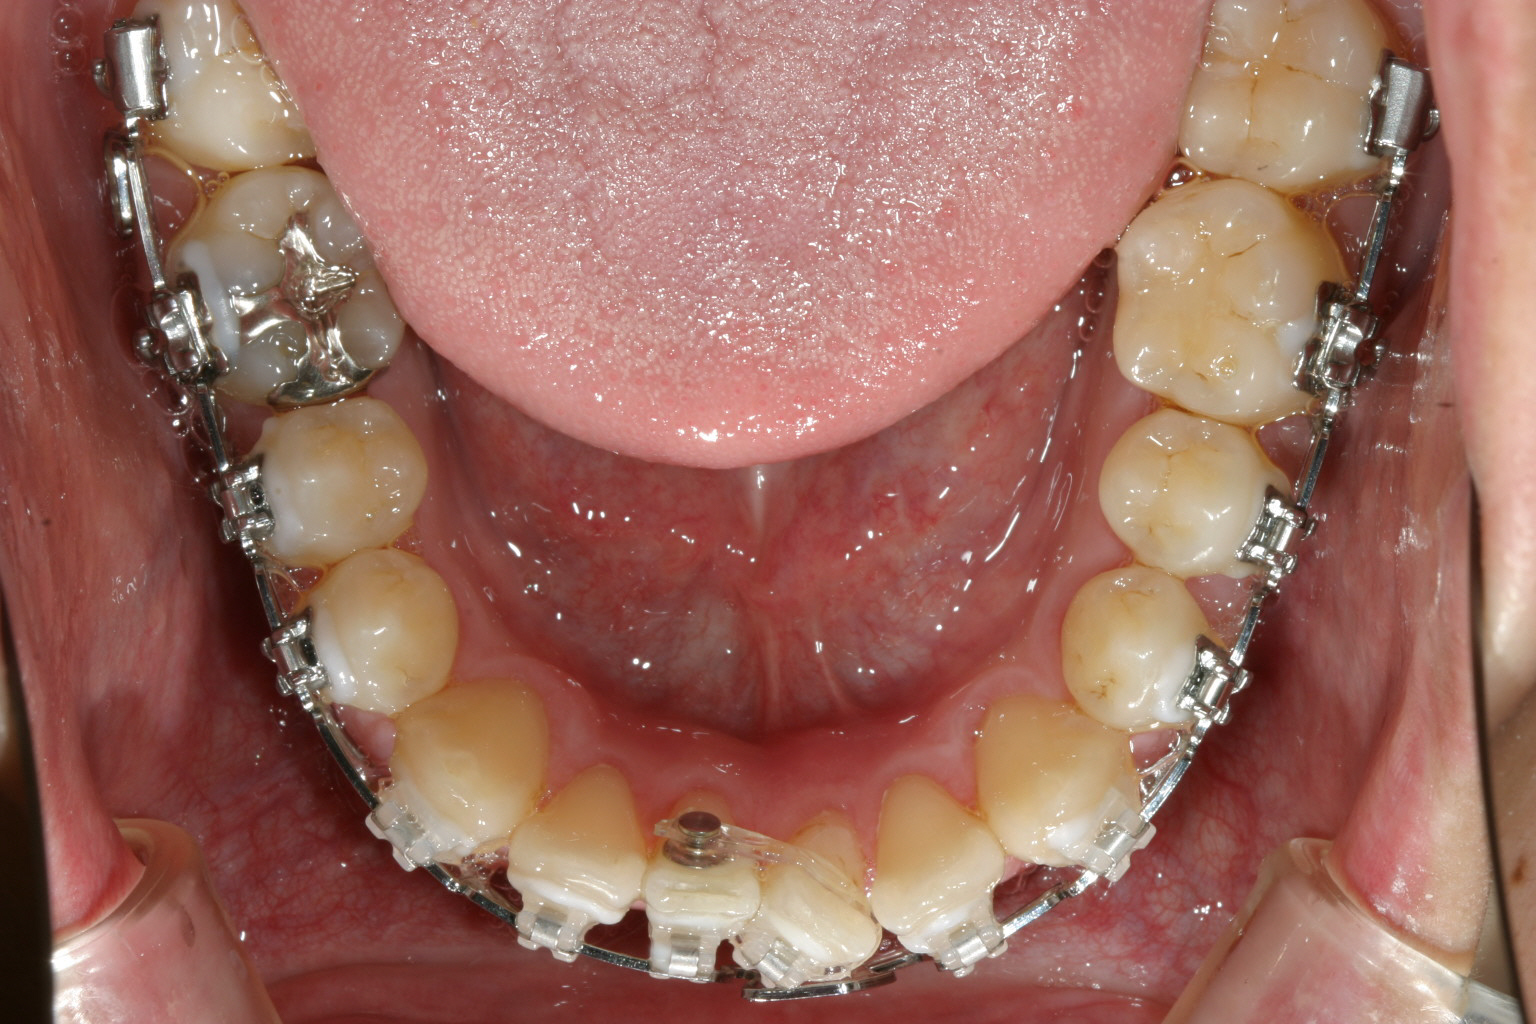

半年後です。右側の2番目の歯の叢生がだいぶ取れてきました。

下顎もかなり綺麗になって来ましたが左下1番の歯の回転で手こずっています。